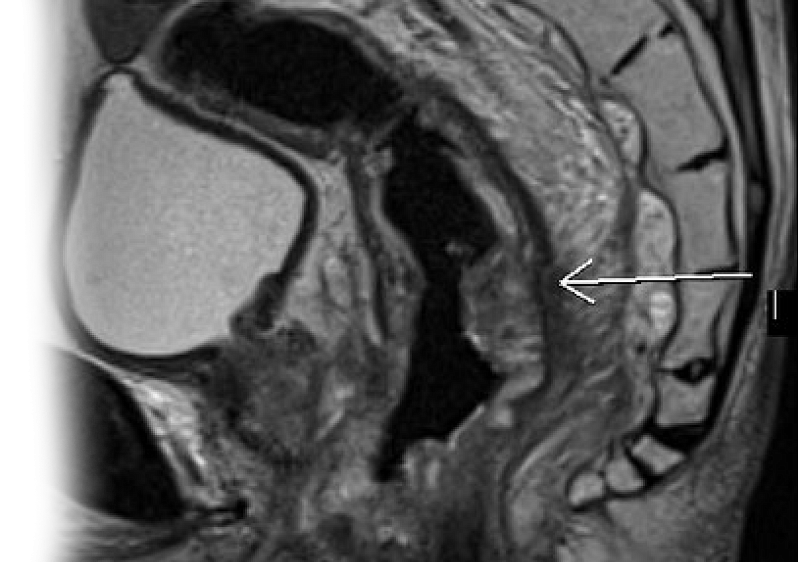

МР исследование прямой кишки и органов малого таза – важный метод исследования, который позволяет визуализировать все отделы прямой кишки, окружающие мягкие ткани, предстательную железу, семенные пузырьки, мочевой пузырь.

Как проводится МРТ прямой кишки и органов малого таза?

Перед укладкой в томограф необходимо снять все металлические предметы. После этого пациент ложится на стол сканера, который постепенно перемещается в аппарат. Во время сканирования следует лежать неподвижно, чтобы получаемые изображения были четкими и неискаженными.